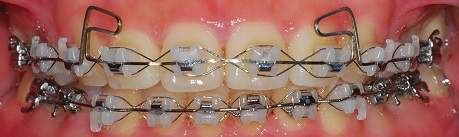

정면사진

예전에는 윗니와 아랫니를 다물었을 때 공간이 있었는데 지금은 아예 없어졌어요~